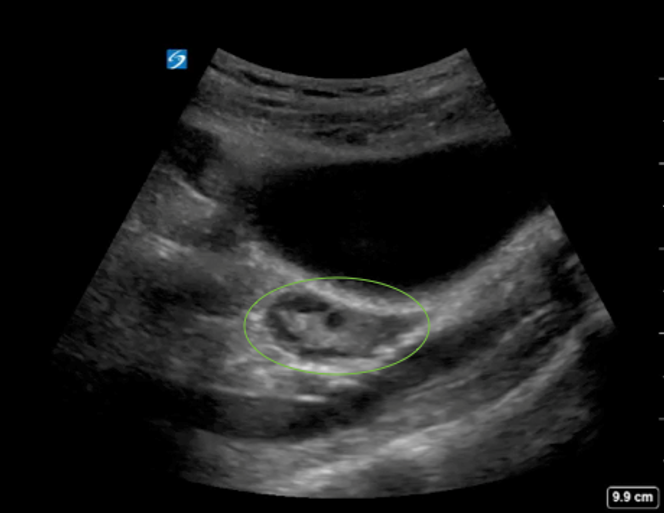

Pelvic Ovary Highlighted Image

Circled Area: Ovary